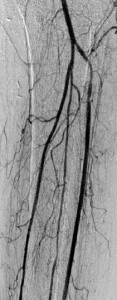

Key to images:

Top panel: Pre-intervention run-off angiogram of the left lower extremity showing, from left to right, irregular left common femoral artery (LCFA) arrowed on the 1st image, absent left superfical femoral artery (LSFA) or any bypass conduit on the 2nd image, sketchy descending collaterals from the left deep femoral (LDFA) that reconstitute a faint shadow of the left popliteal artery, arrowed on the 3rd image. The last 2 images faintly show three-vessel run-off below the left knee. The anterior tibial artery is most opacified, followed by the posterior tibial artery; the peroneal artery peeps through the upper edge of the last image. Note how weakly visible these vessels are due to the poor inflow from above.